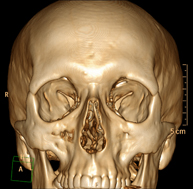

- TC Macizo facial  Prueba radiológica que consiste en obtener imágenes del macizo facial (cara) de alta definición anatómica mediante el empleo de un equipo de TC (Tomografía Computarizada). Indicaciones: tumores, cirugía plástica. Prueba radiológica que consiste en obtener imágenes del macizo facial (cara) de alta definición anatómica mediante el empleo de un equipo de TC (Tomografía Computarizada). Indicaciones: tumores, cirugía plástica.